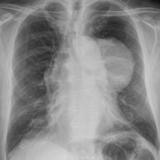

Case 9 Thymoma PA

Date: 04/04/2010

Views: 3164